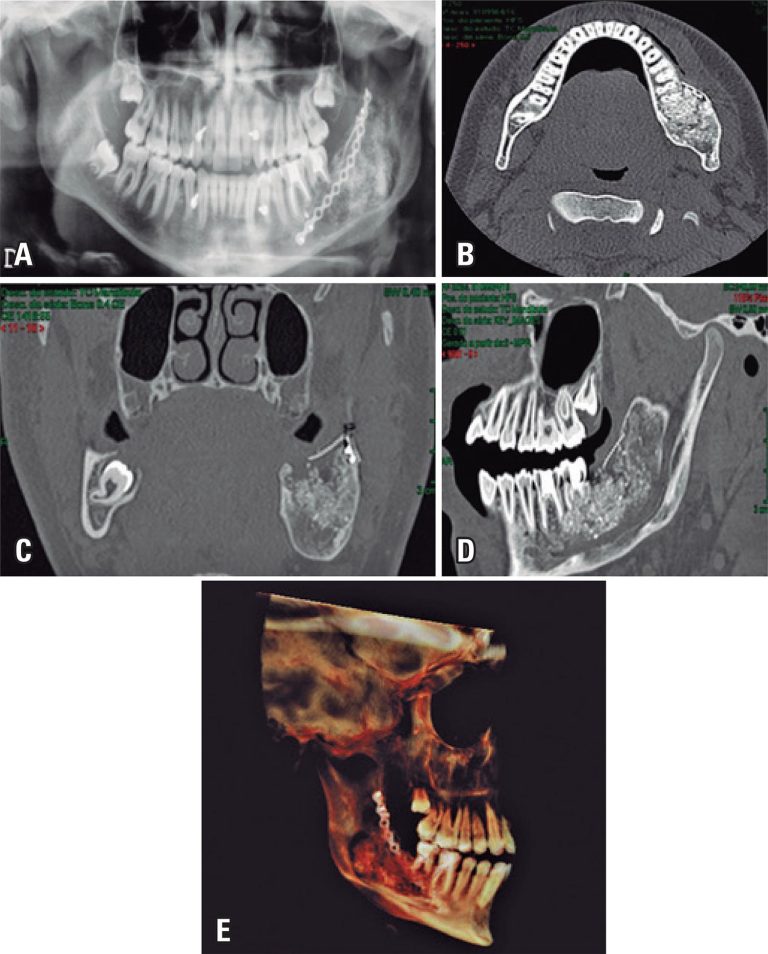

Off-label use of rhBMP-2 as bone regeneration strategies in mandibular ameloblastoma unicystic

Jawbone reconstruction after tumor resection is one of the most challenging clinical tasks for maxillofacial surgeons. Osteogenic, osteoinductive, osteoconductive and non-antigenic properties of autogenous bone place this bone as the gold standard for solving problems of bone availability. However, the need for a second surgical site to harvest the bone graft increases significantly both the cost and the morbidity associated with the reconstructive procedures. Bone grafting gained an important tool with the discovery of bone morphogenetic proteins in 1960. Benefit of obtaining functional and real bone matrix without need of second surgical site seems to be the great advantage of use bone morphogenetic proteins. This study analyzed the use of rhBMP-2 in unicystic ameloblastoma of the mandible, detailing its structure, mechanisms of cell signaling and biological efficacy, in addition to present possible advantages and disadvantages of clinical use of rhBMP-2 as bone regeneration strategy.